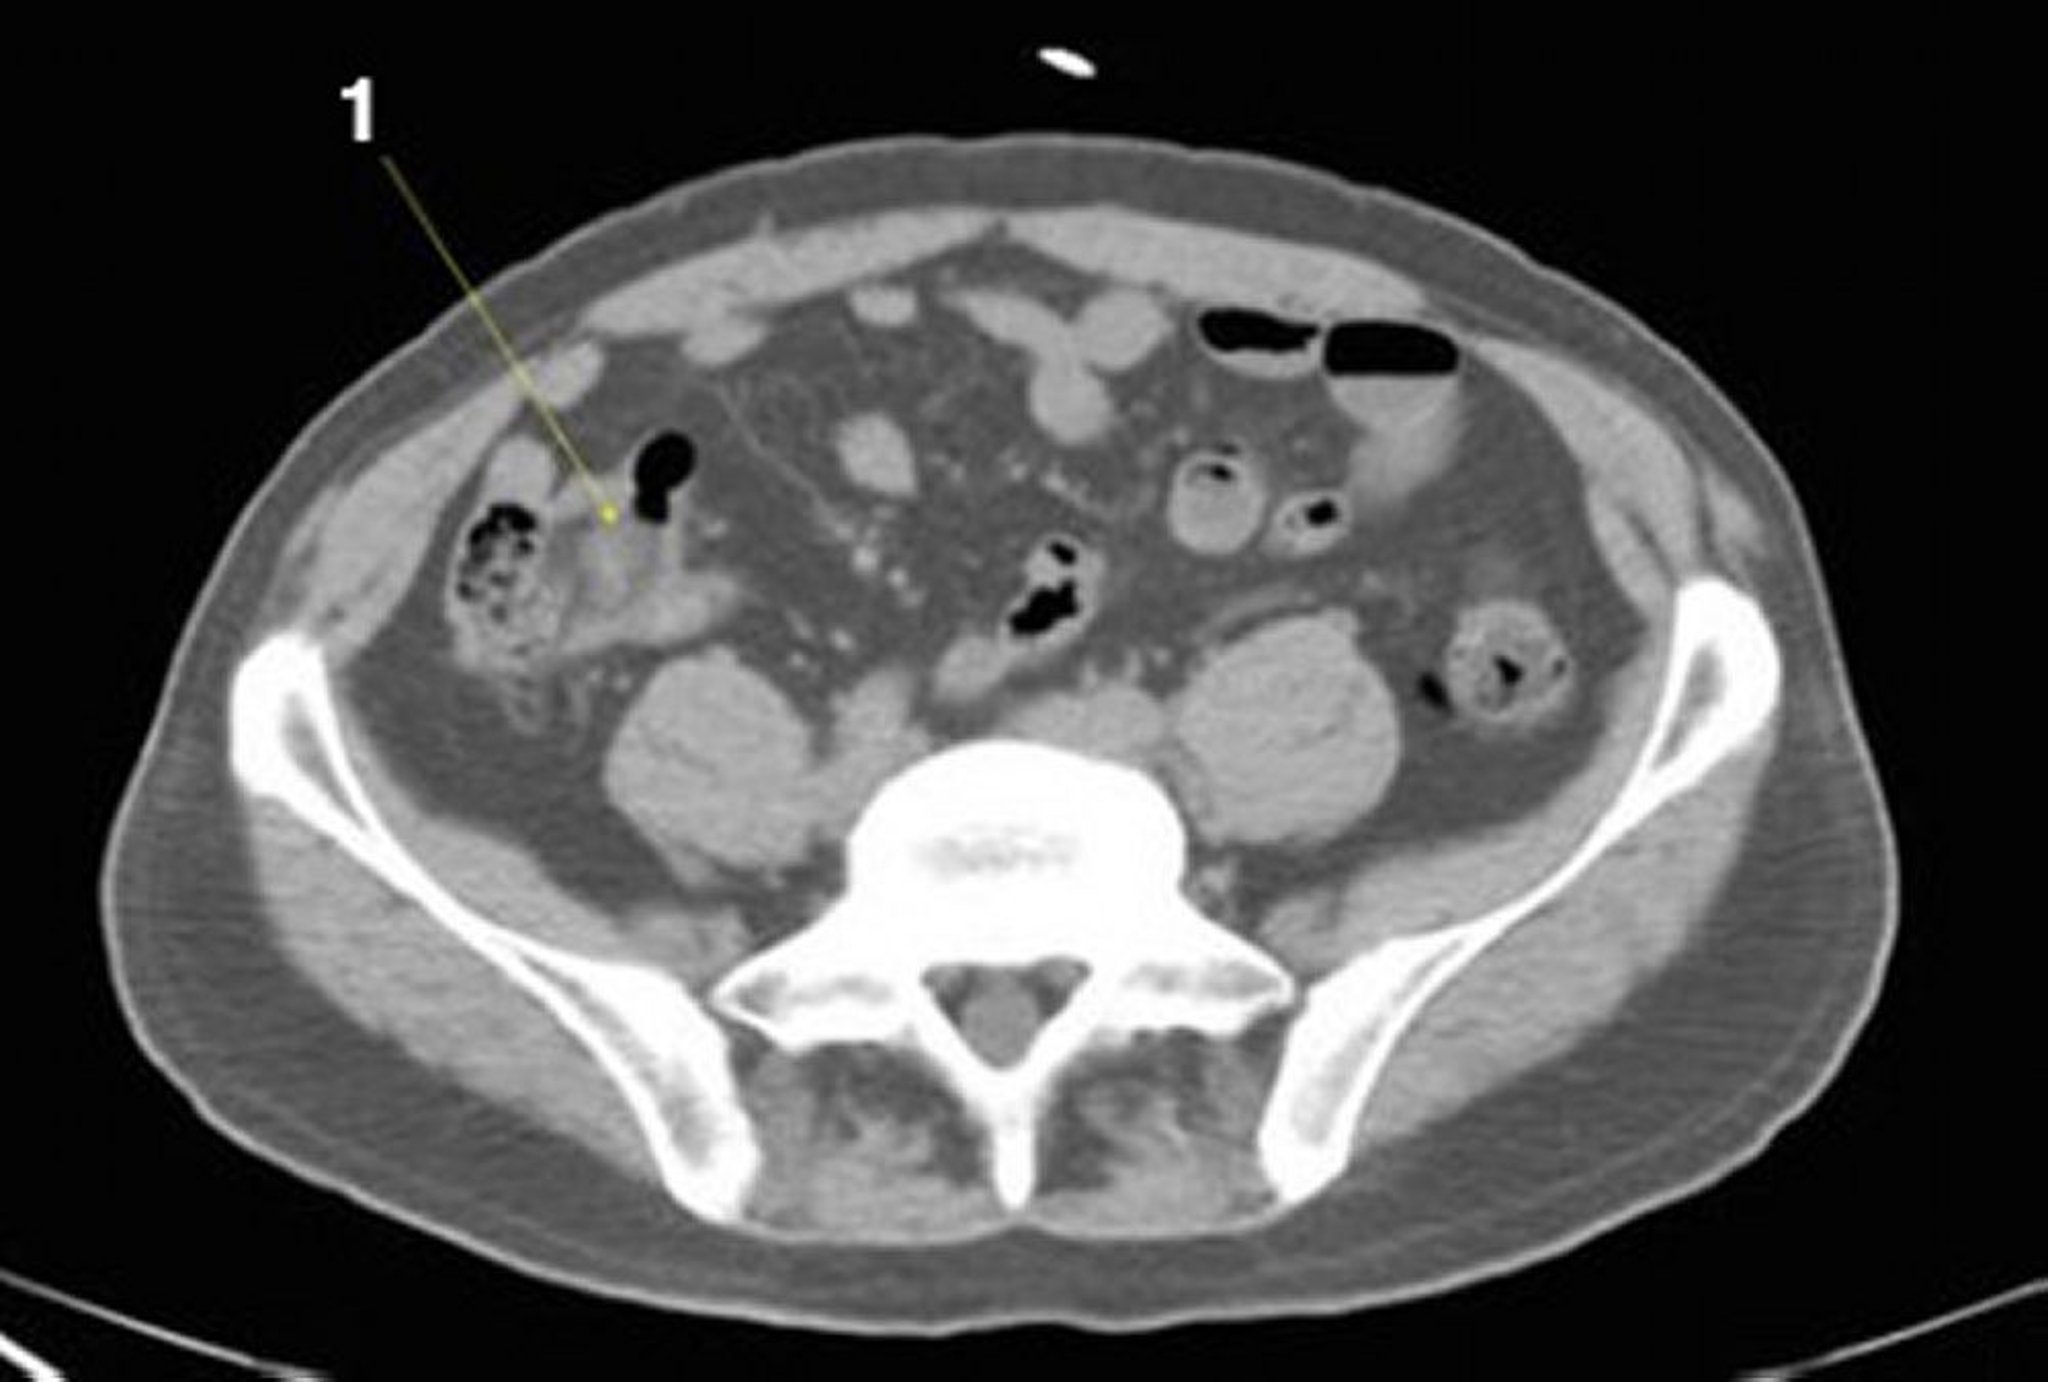

Noncontrast CT Scan of the Abdomen and Pelvis Showing Normal Anatomy (Slide 21)

1 = ileum.